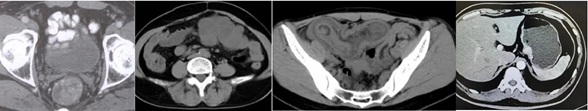

阿梵D胃肠疾病(结肠癌)临床案例分享

↑胃肠病灶切除分析

让手术更精准,让患者更好生活